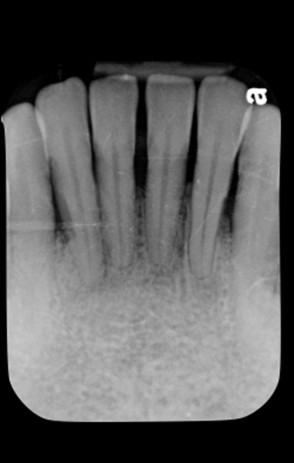

Fig 5. Initial radiograph of the Case 1 patient, teeth Nos. 22 through 27.

Figure 5